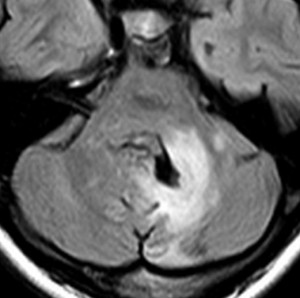

中脳視蓋毛様細胞性星細胞腫 tectal glioma(詳しくはここをクリック)

中脳視蓋グリオーマとして知られるものです。この腫瘍は基本的には,初回手術で全摘出できるのですが,現実的には,技術的に難しすぎるので部分摘出で終えることが多いでしょう。この子は,15歳の時に閉塞性水頭症のために,頭痛,嘔吐,意識障害,瞳孔不同となりました。開頭部分摘出術と第3脳室開窓術で回復して,その後にカルボプラチンとビンクリスチンの化学療法を受けました。でも腫瘍増大が止められずに,発症1年後に54グレイ30分割の放射線治療を受けています。さらにその半年後くらいから再増大しましたが,スードプログレッションと考えられました。のう胞性拡大が止まらず,発症3年後にまた再開頭手術で亜全摘出しました。